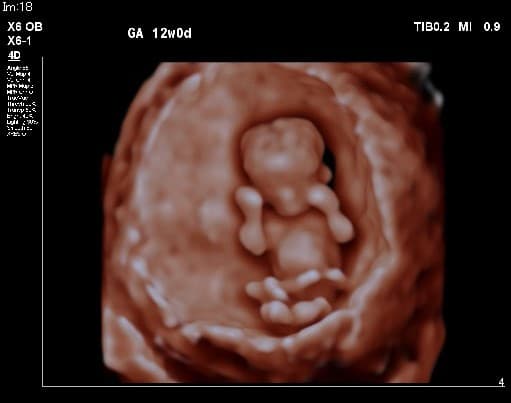

母と子のまきクリニック(Mother and fetus Maki Clinic)は、全国でも数少ない『出生前検査』の専門クリニックで【NIPT認証施設】です。妊婦健診や一般不妊治療、婦人科では小児期から、10~20代では将来を考えた『プレコンセプションケア』、更年期まで様々な女性の健康をサポートしています。 出生前検査の中でも、実施できる施設の少ない『胎児超音波精密検査(胎児ドック)』は、妊娠初期から可愛い赤ちゃんの様子や4D超音波を見て頂きながら、多くの先天性の病気のチェックができ、当日のうちに結果がでる検査です。 ・母体血による検査(NIPT・コンバインドテスト;オスカー検査)<日本医学会NIPT認証施設> ・胎児超音波精密検査(プレドック、初期・中期・後期胎児ドック)<英国FMF超音波資格> ・安全迅速な確定診断(絨毛検査・羊水検査による染色体・遺伝子検査) ご家族で初めて赤ちゃんに出会える!当院ならではの感動の出生前検査です。検査結果に合わせて赤ちゃんをしっかり診させていただき、尊い命を大切に育みながらご家族一緒にマタニティライフを楽しんで頂けるよう願っています。